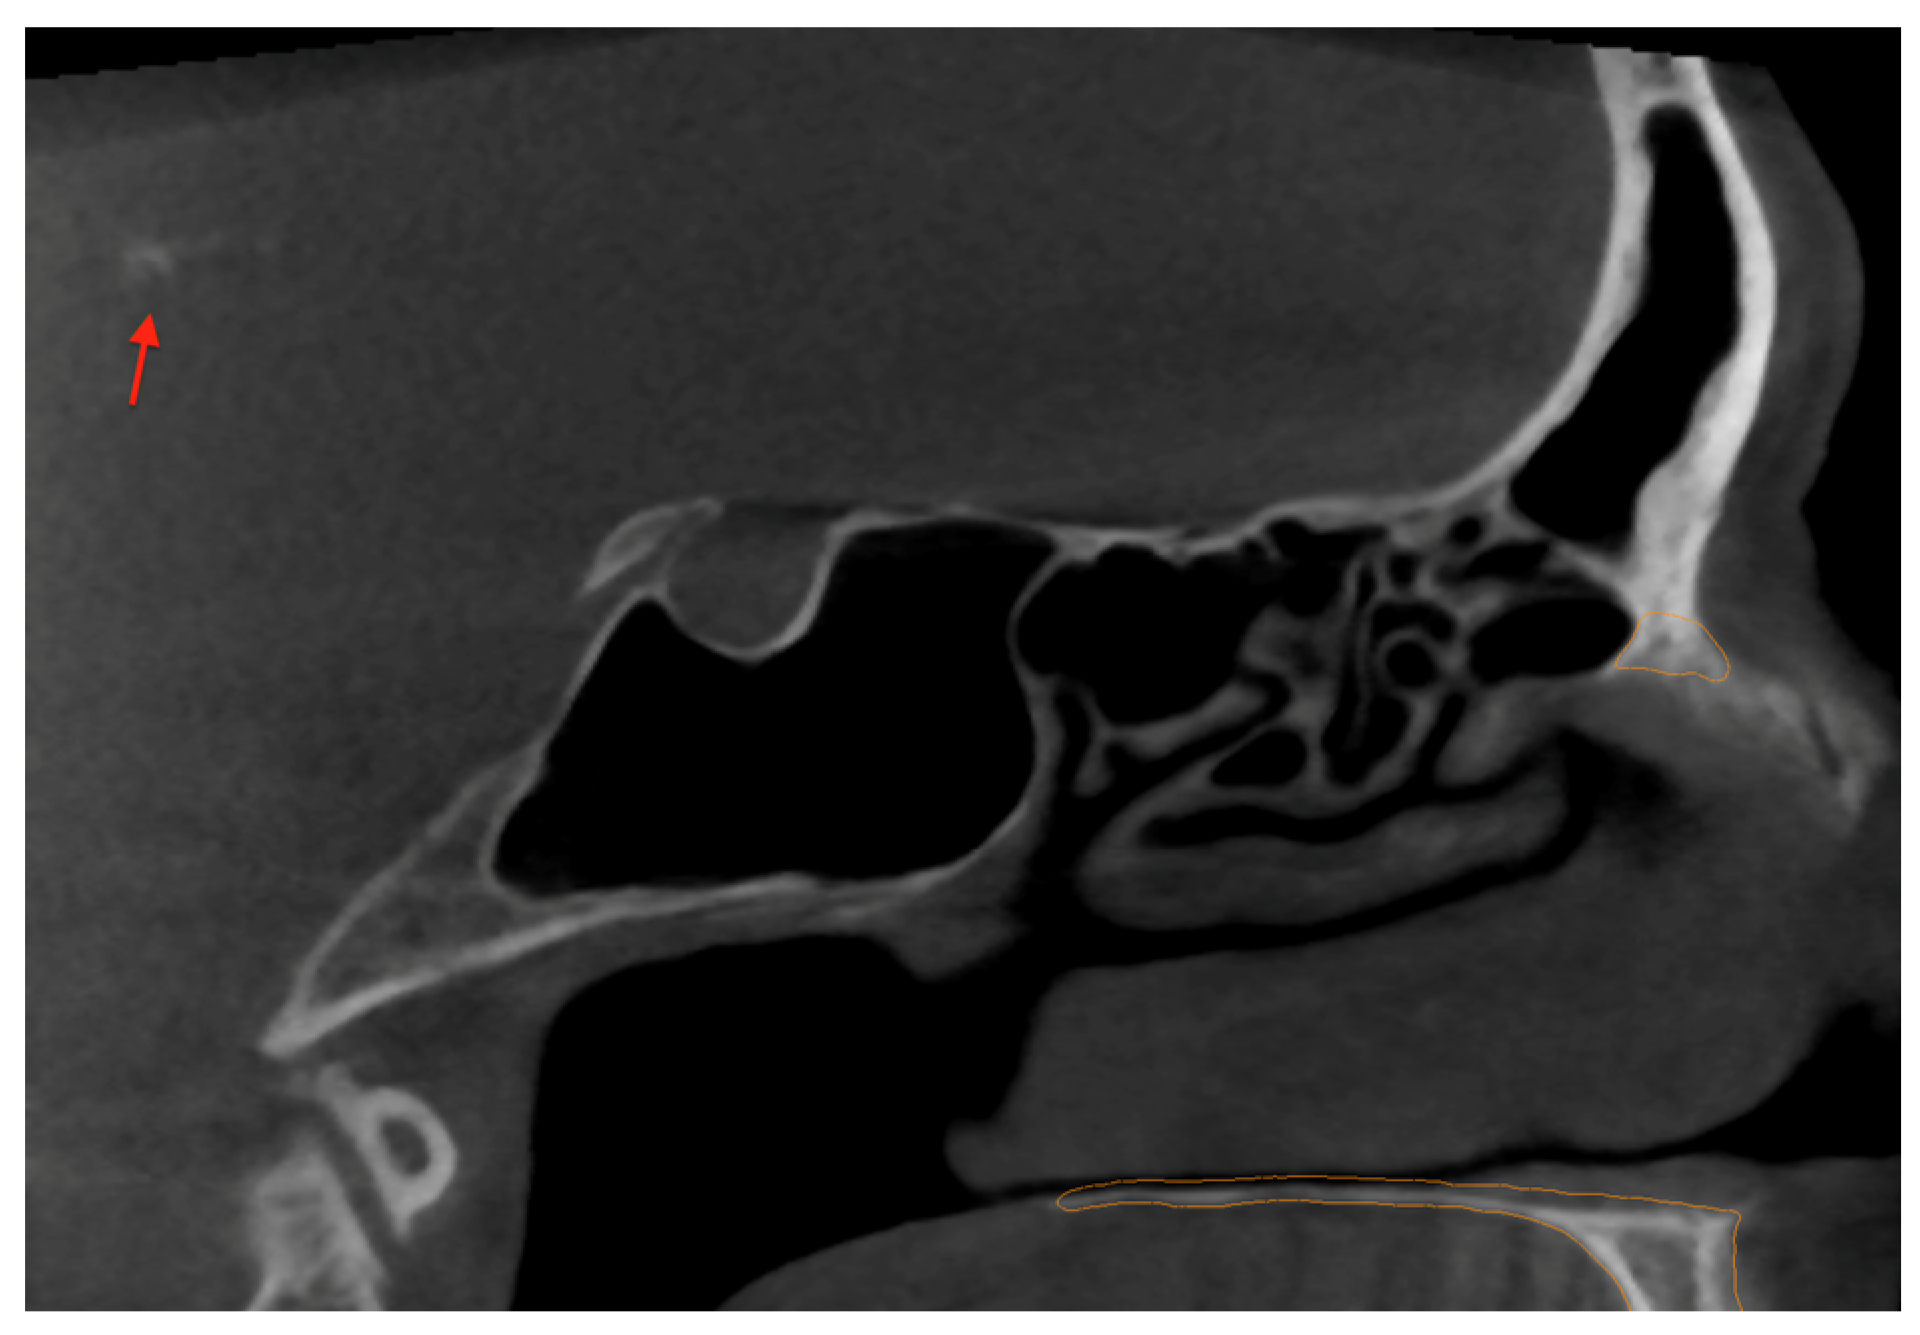

2. Case Report and AI Application